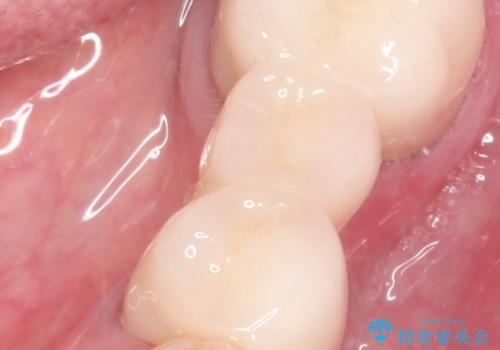

金属のかぶせ物をセラミックへ 根管治療からの再治療

左側の上下の奥歯に適合が悪く、レントゲン上でも根の治療が必要なところがありました。

根管治療からの再治療を行ったことにより、治療期間が多少長くなりましたが、今後再治療の必要性があまりないような、精度の高い治療ができました。